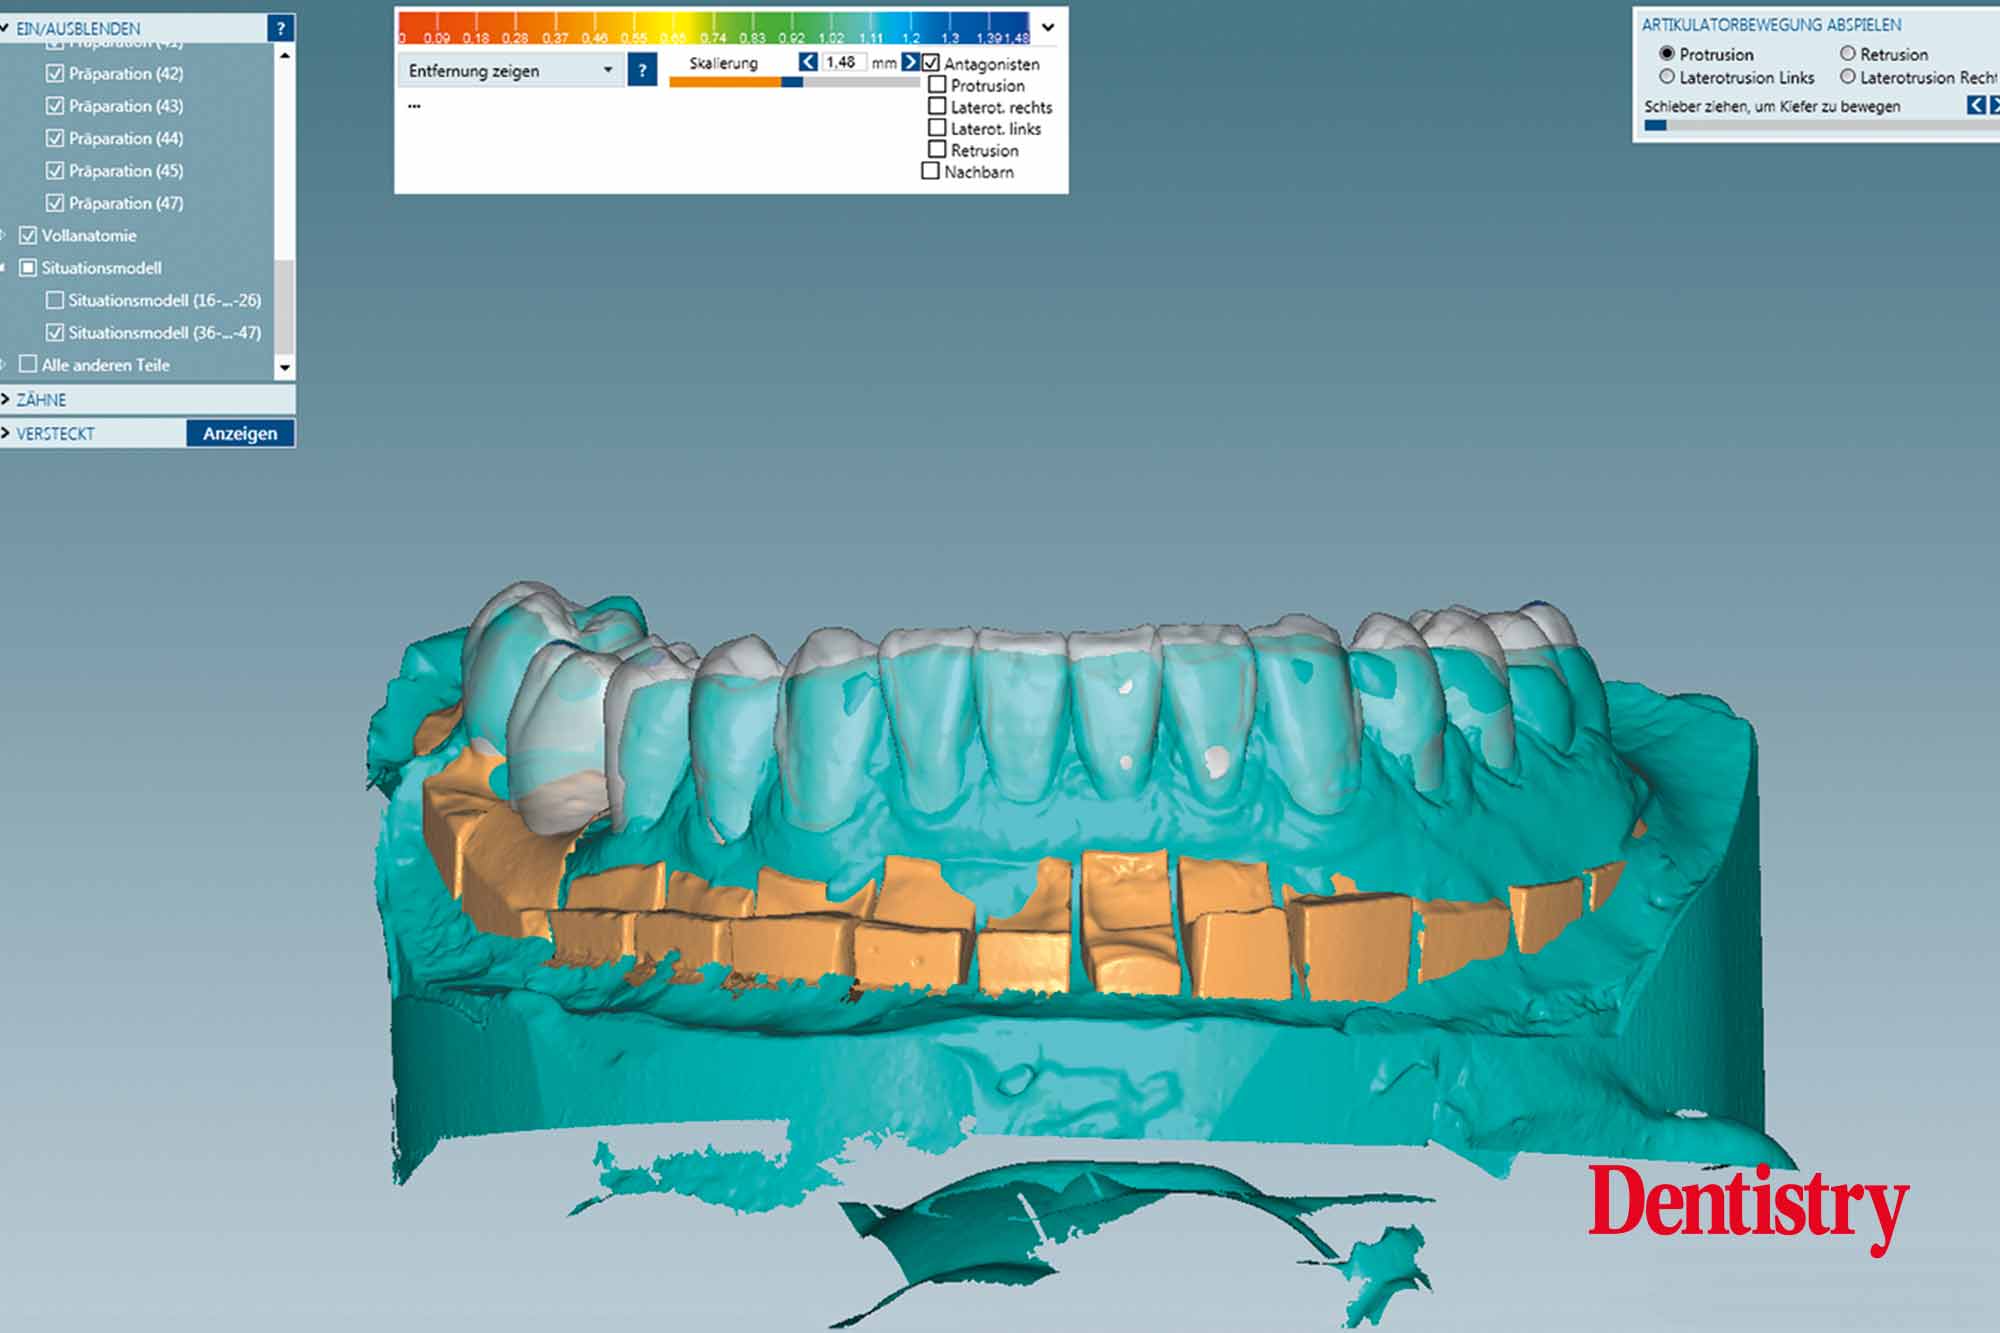

The scanned models were evaluated on a virtual 11 articulator. Temporary Ceramill PMMA (Amann Girrbach) transparent acrylic crowns were CAD planned (Figures 3a to 3d).

Patient data including condylar movements were recorded by the software. Using the Initial situation software’s customised incisal guide unit, the incisal guide pin was adjusted on the splitex plate to the desired cuspal inclinations on the virtual temporary crowns (Figure 4).

All patient parameters including condylar inclination were transferred to the Ceramill Artex articulator and the lateral and protrusive excursions were established while having no contact with the anterior teeth (Figures 5 to 8).